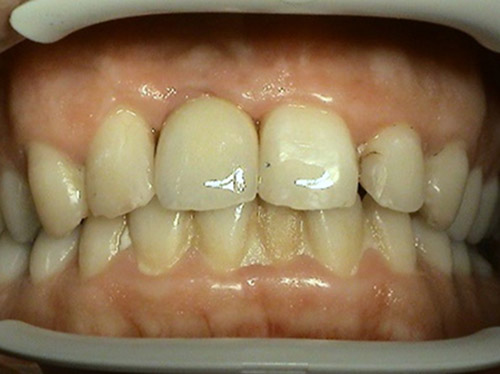

2. PHASE – state before making immediate impressions

3. PHASE – prosthetic fabrication of temporary crown on implant

3. PHASE – fabrication of temporary solution